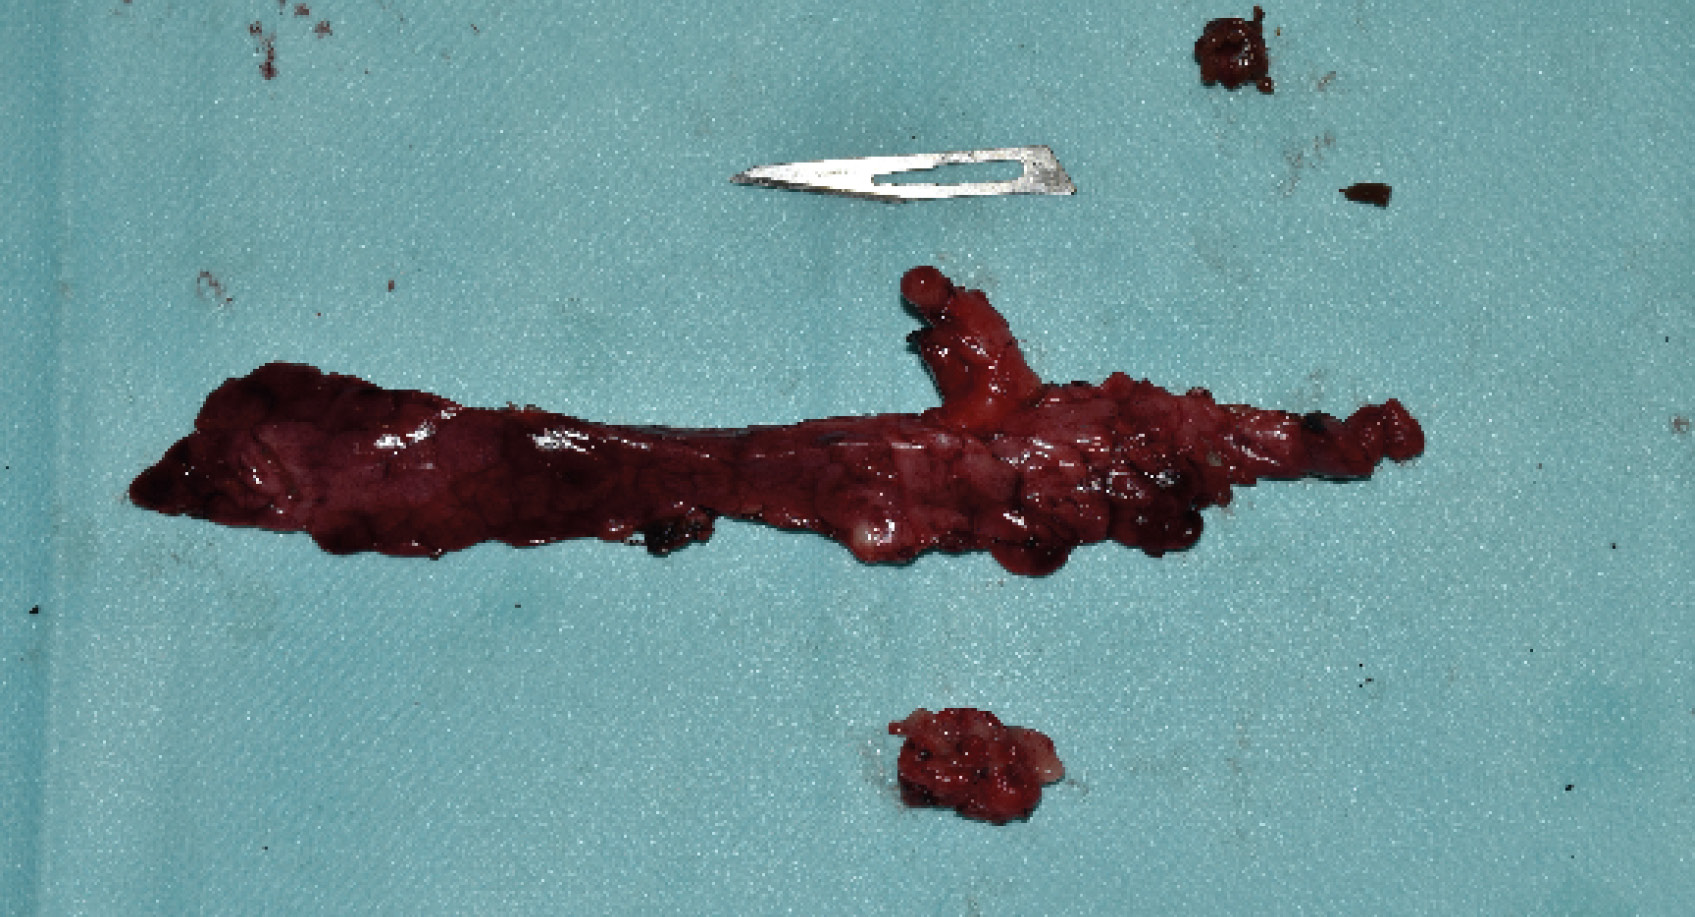

Posteriormente, se realizó linfadenectomía pancreático-duodenal y la biopsia de dos lesiones hepáticas localizadas en el lóbulo lateral y medio derechos. Tras lavar el abdomen con solución salina estéril atemperada, se realizó el cierre de la cavidad abdominal de forma rutinaria en tres capas: muscular, subcutáneo y piel. Los tejidos extirpados fueron enviados al laboratorio para su estudio histopatológico (imagen 3).

El estudio histopatológico del nódulo pancreático reveló un carcinoma neuroendocrino de los islotes pancreáticos (insulinoma) donde se apreció infiltración del trombo tumoral, junto con un foco metastásico en la muestra de hígado. No se detectaron células neoplásicas metastáticas en las muestras de nódulos linfáticos remitidos para su estudio.